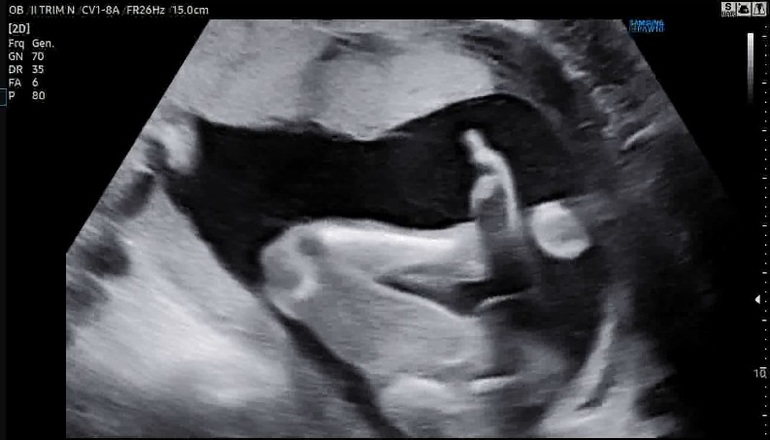

Фото с узи

Личико и рука